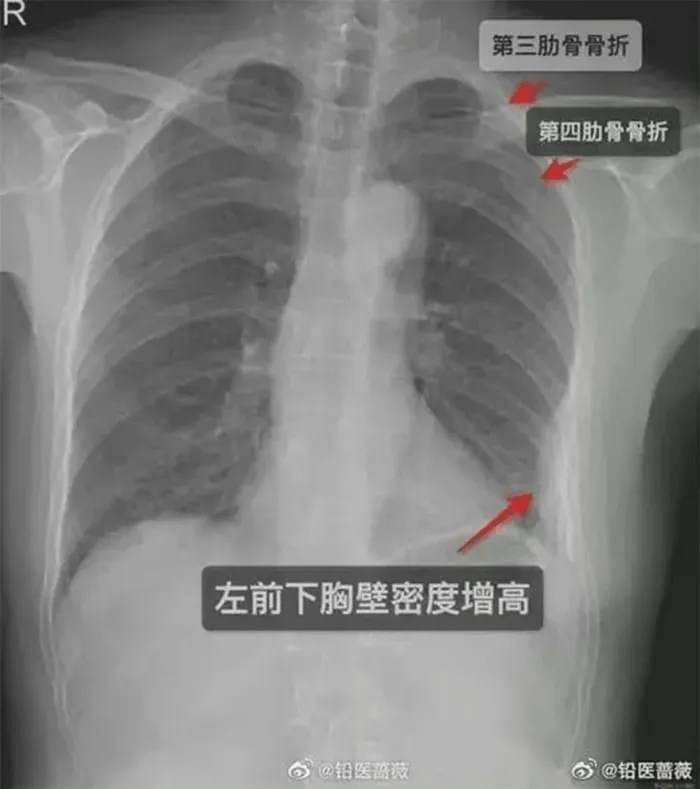

Vào ngày thứ 5 sau sự việc trên, do đau đớn đến không thể chịu nổi, cô gái mới đến bệnh viện khám và hoảng hốt khi bác sĩ cho biết cô bị gãy 2 xương sườn trước bên phải và một xương sườn bên trái.

Tòa kết luận rằng cái ôm của nam đồng nghiệp đã khiến cho cô gái bị gãy 3 cái xương sườn, do đó anh ta phải bồi thường 10.000 tệ (gần 35 triệu đồng). Dù thương tích của cô được phát hiện sau cái ôm 5 ngày, tòa cho rằng không có chứng cứ nào chứng minh trong 5 ngày đó, cô gái có những hành động hay gặp sự cố gì dẫn đến gãy xương sườn. Hơn thế, những đồng nghiệp khác cũng đã làm chứng rằng cô gái tỏ ra đau đớn và hét lên khi bị ôm.